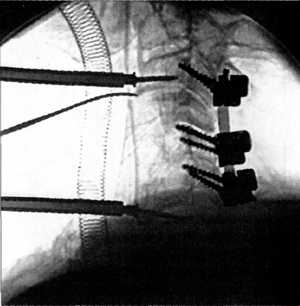

применения halo-аппаратов с тех пор значительно расширилась. Действие конструкции

основано на создании скелетной тяги с помощью четырех стержневых фиксаторов,

внедренных в кости черепа в пределах наружного кортикального слоя и диплоэ и

закрепленных в окаймляющем череп кольце. Опора создается на штанги, соединенные

с базовым тораколюмбальным блоком.